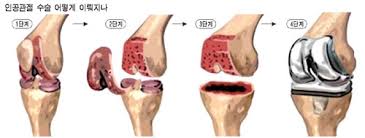

무릎 인공관절수술비용이 궁금하신가요? 퇴행성 관절염 등으로 무릎 인공관절 수술을 고려하는 분들이 많은데, 비용은 건강보험 여부, 병원급, 선택진료 옵션, 장비 사용(로봇) 등에 따라 크게 달라집니다. 국내 비용부터 의료관광 비용, 보험 적용 여부까지 자세히 알려드립니다.